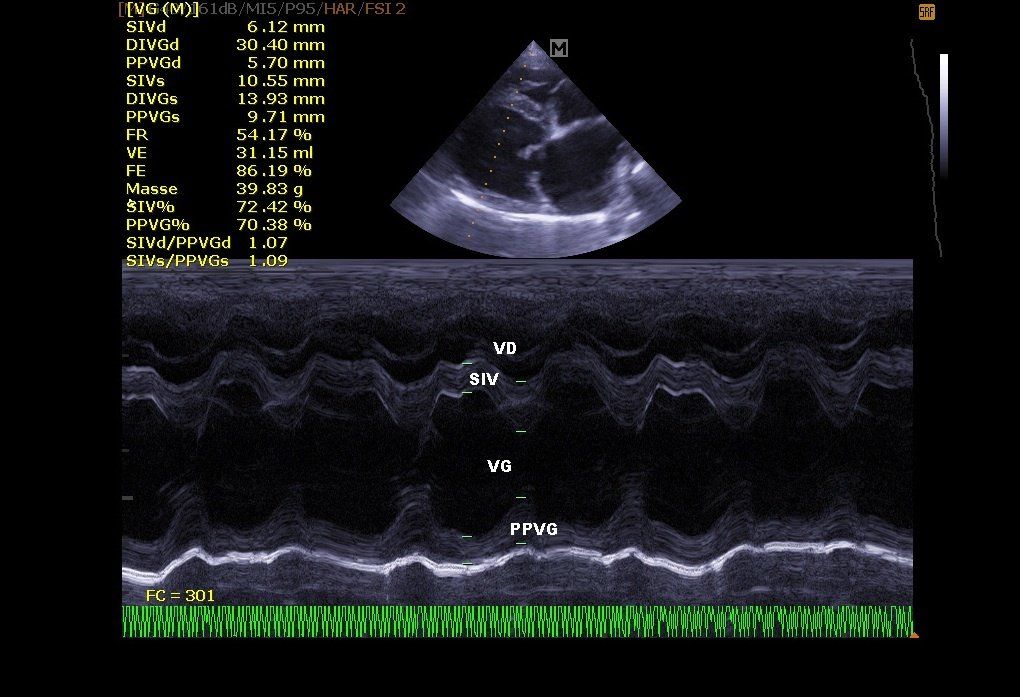

Echocardiography:

It makes it possible to visualize the different parts of the heart (walls, cavities, valves) and to identify any anomalies that prevent correct cardiac functioning. In case of heart failure, echocardiography also allows regular monitoring of cardiac morphology. It is then easier to readjust the treatment in place.